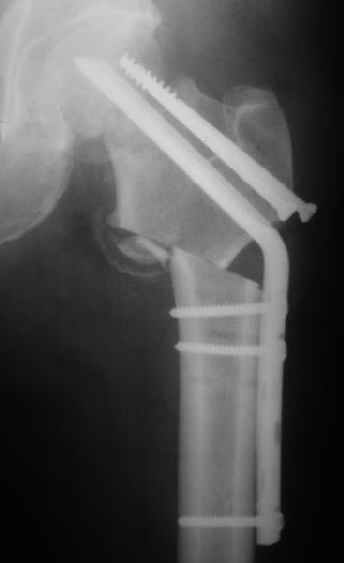

Мужчину 56 лет оперировали у нас в августе 2003 г. - вальгизируюшая остеотомия из-за позднего (через 2 мес. после травмы) поступления с переломом шейки бедра (картинки 1,2). Курильщик, соматической патологии не было. Сейчас поступил с жалобами на проблемы в области тазобедренного сустава, на снимках 3,4 видно вырезывание клинка.Чтоб можно посоветовать в этой ситуации? Заранее спасибо.

A male 56 years old was operated in Aug 2003 - valgus osteotomy performed because of delayed admission with neck fracture (2 months) images 1,2. Smoker, no other major medical problem. Now he re-admitted with the images 3,4.What would you do in the situation?THX in advance.